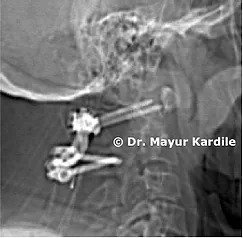

A 61-year-old gentleman with rheumatoid arthritis complaining of neck pain and gait instability. He also had clumsiness of hand movement and spasticity.

Investigations revealed instability between the first and second cervical vertebra causing dynamic compression of the cervical spinal cord.

C1 - C2 stabilization and fusion were done using C1 lateral mass and C2 translaminar screw fixation. Postoperative CT scan and X-ray show good C1 - C2 reduction.